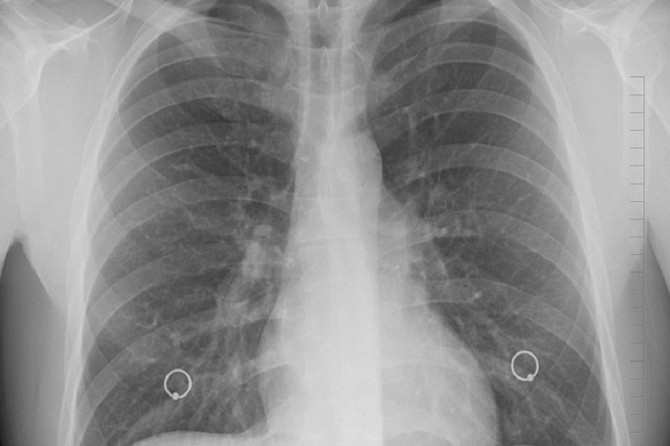

По словам специалиста, сохраняющийся кашель уже после получения отрицательный тестов на коронавирус может говорить о развитии хронической обструктивной болезни легких (ХОБЛ). В итоге может возникнуть эмфизема, при которой стенки альвеол истончаются и могут замещаться соединительной тканью, приводя к фиброзам, пишет «МК».

Длительный кашель приводит к ослабеванию мышечной стенки бронхов и образованию мешочков — бронхоэктазов, которые скапливают мокроту. Из-за этого кашель не прекращается. В итоге это может привести к множеству осложнений, в том числе спонтанный пневмоторакс.